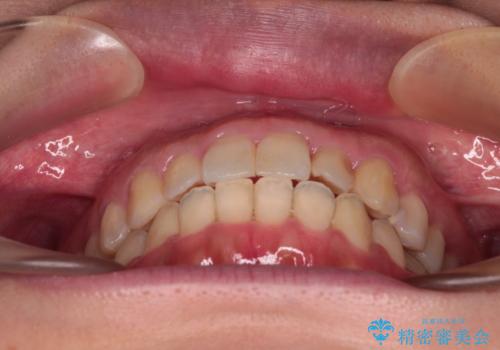

- 前歯の捻れを気にして来院された患者様です。

上顎前歯が捻れて前方に飛び出しており、下顎前歯もそれに沿うようにデコボコとなっていました。

IPR(歯と歯の間を削る処置)によりスペースを獲得して上下前歯のデコボコを改善し、インビザラインにて矯正治療を行うこととしました。

捻れていた前歯の形態が、先端が欠けていたり、一部むし歯処置により左右非対称の形態となっていたため、なかなかゴールが定まらず、治療期間がかかってしまいました。